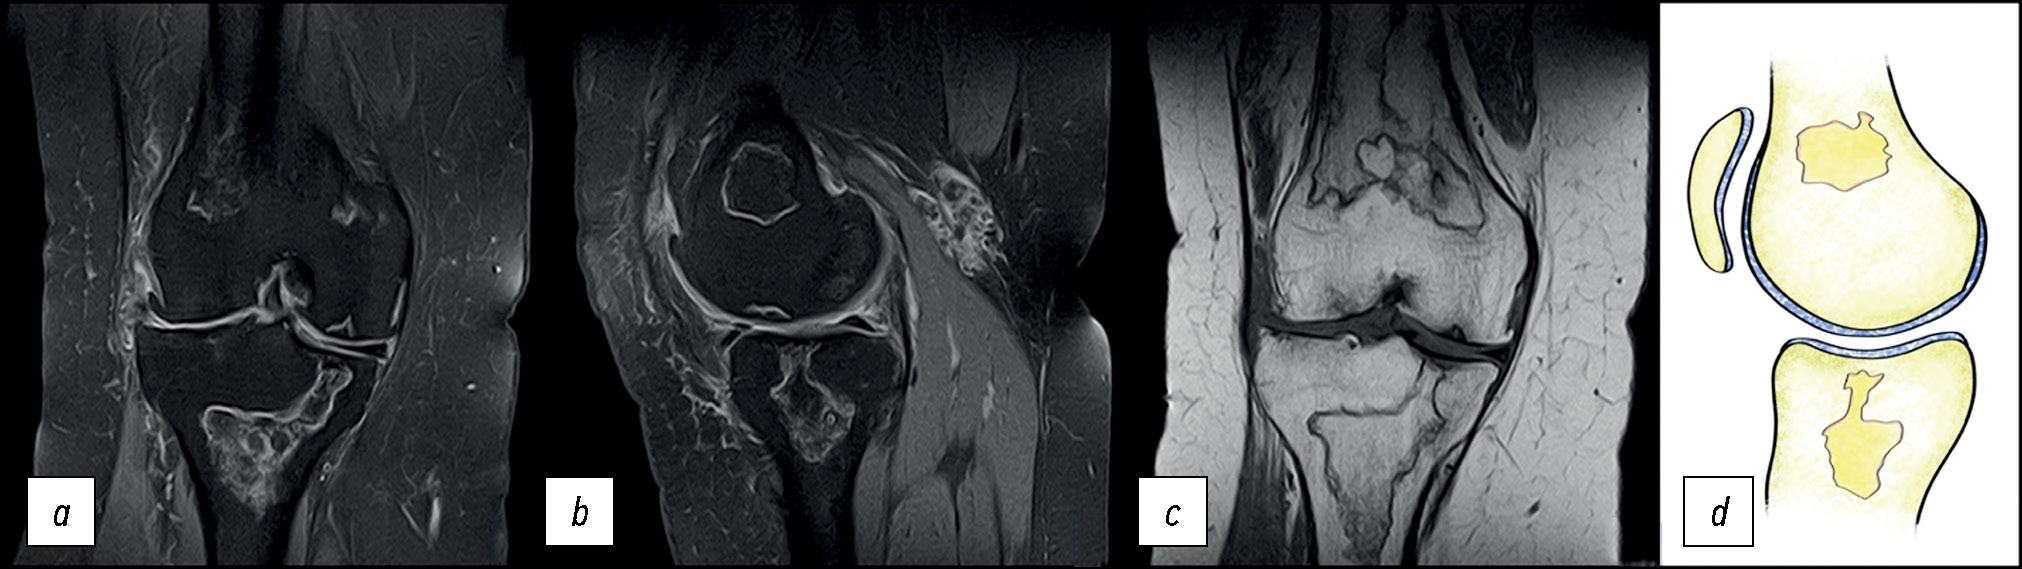

На выполненных рентгенограммах патологии не выявлено. Пациент наблюдался в клинике по месту жительства с диагнозом «остеоартрит коленного сустава». В связи с неэффективностью применения нестероидных противовоспалительных препаратов выполнил МРТ-исследование, на котором выявлен отёк костной ткани в области наружного мыщелка бедренной кости (рис. 1), плавно переходящий на внутренний мыщелок.

Рис. 1. МР-томограммы коленного сустава: а, b — изображение в T2w-STIR режиме, с — изображение в режиме Т1 в корональной проекции, и графическое изображение остеонекроза мыщелка в сагиттальной проекции (d).

Fig. 1. MR images of the knee: а, b — T2-weighted short-tau inversion recovery (T2w-STIR), с — T1-weighted sequences in the coronal projection and a graphic image of an osteonecrosis (d).

Состояние расценено как идиопатический асептический некроз наружного мыщелка бедренной кости I стадии по классификации ARCO (остеонекроз) (M87.0) [8].

Особенности отёка костной ткани: достаточно равномерный, без каких-либо линий и включений, распространяется на большую часть мыщелка. Гиалиновый хрящ не вовлечён в патологический процесс, имеет ровную поверхность без деформации, что характерно для начальной стадии асептического некроза [9].